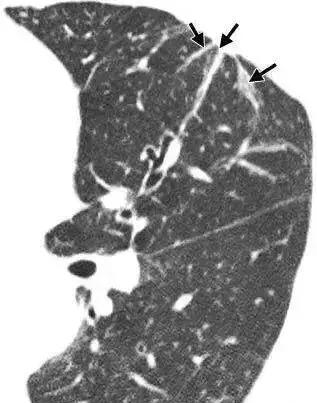

肺纹理增多(或者是增重/增加/增强)

肺纹理由肺动脉、肺静脉、支气管、神经、淋巴管等结构组成。造成肺纹理增多的常见原因有:

▶ 支气管性纹理增强——常见于支气管炎

▶ 血管性纹理增强——常见于心脏病变引起肺血改变

▶ 淋巴性纹理增强——常见于淋巴管炎、淋巴管转移

▶ 生理性肺纹理增多——常见于老年人和肥胖者

总的来说肺纹理增多这个诊断主观性较强。导致肺纹理增多的原因也有很多种,有病理性的,也有生理性或技术性的。孤立地报告肺纹理增多,临床价值不大。只有认真的分析肺纹理增多的具体性质和原因,并且与其他影像学特征、临床病史及技术条件结合起来综合考虑,才能得出正确的结论。

Fig 1 肺纹理增多(箭头所示)